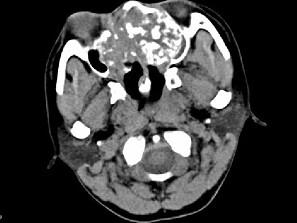

男,26岁,进行性鼻腔阻塞、流涕来院就诊,近两年持续性头痛、头晕,如图所示筛窦区占位灶应诊断为 ( )